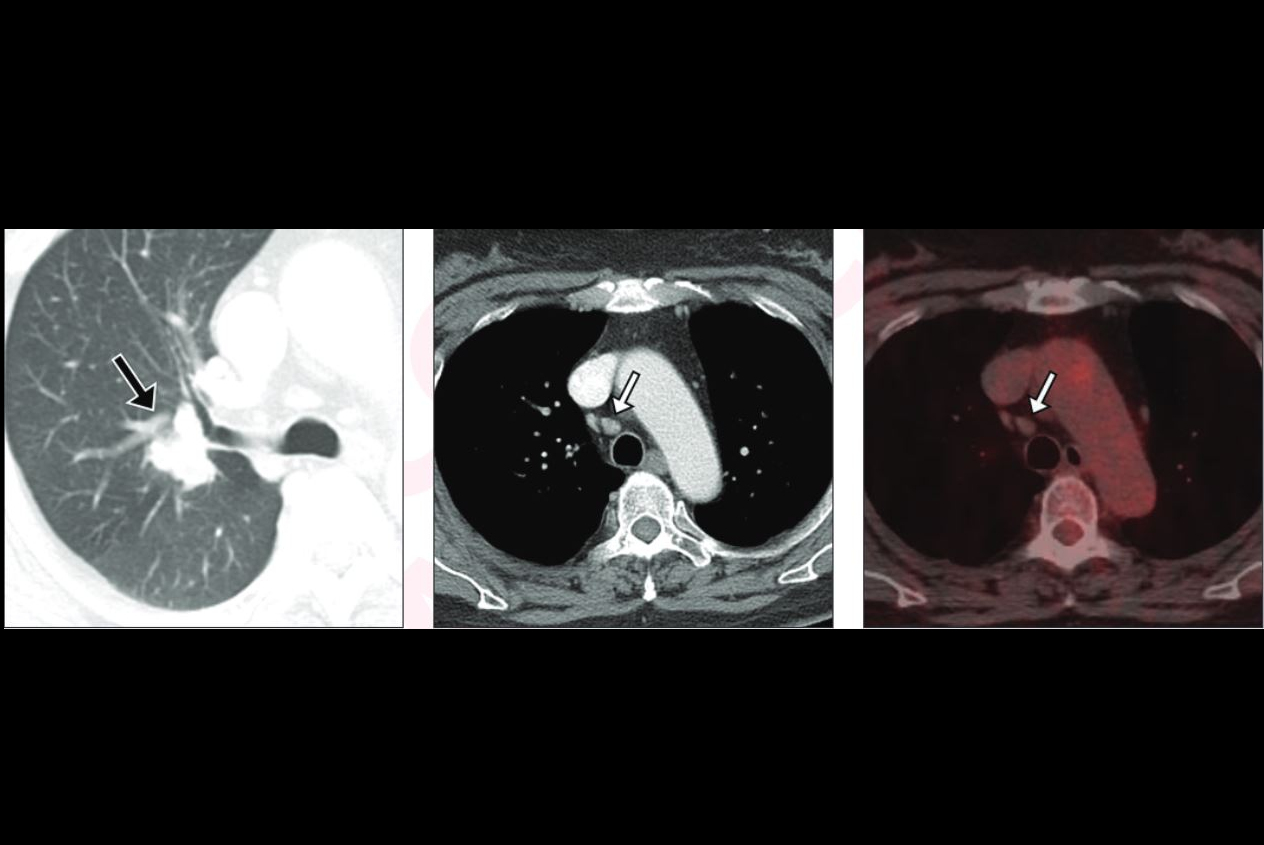

CT

CT is the "mainstay" for characterizing pulmonary nodules, Shaish noted. These exams are conducted with or without contrast, and they can provide information on nodules' shape, size, density, calcification, location, and morphology (ground glass, part solid, oval solid, solid). They also help clinicians assess nodules' margins -- smooth, lobulated, and spiculated.

F-18 FDG-PET/CT

When it comes to characterizing lung nodules using PET/CT, clinicians can look for the following results:

• A high standardized uptake value (SUV) -- more than 2.5 -- suggests malignancy.

• Low/no uptake suggests that the nodule is benign.

• Intense, irregular uptake suggests higher suspicion of malignancy.

PET/CT's advantages for lung nodule imaging include a high sensitivity for malignancy (85% to 95%) and an ability to detect hidden metastases. Its downsides include false positives or negatives, Shaish said.